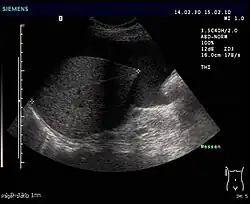

- Sonografie (Ultraschall): Geringe Mengen von Aszites lassen sich dabei am ehesten am Unterrand der Leber oder knapp oberhalb der Harnblase nachweisen. Der Raum zwischen Leber und Niere (Morison-Grube oder Recessus hepatorenalis) ist im Liegen der tiefste Punkt des Oberbauchs.

- Computertomografie